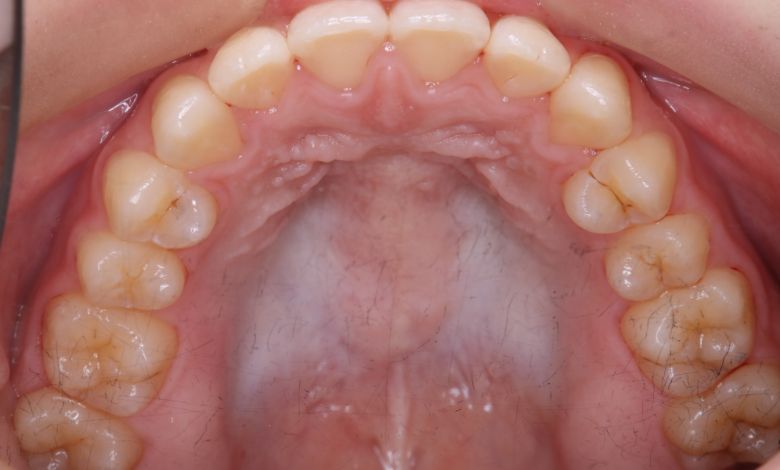

正常な咬合関係が確立され、前歯の自然なアーチと歯軸も整い、歯列全体が滑らかなカーブを描く美しい歯並びに

精密検査の結果、当院では抜歯を行わず、歯列弓の拡大によってスペースを確保し、非抜歯での矯正治療を選択しました。歯列の叢生(ガタガタ)は解消され、機能的かつ審美的に優れた咬合が得られました。

歯列弓はV字型から自然でゆったりとしたU字型へと広がり、唇側に転位していた犬歯も正しい歯列内に整列されています。

歯列弓の側方拡大により適切なスペースが確保され、歯が綺麗に並んでいます

当院では抜歯を行わず、歯列弓を広げてスペースを確保する治療を選択。歯並びは自然なU字型へと整い、前歯の重なりも解消されました。咬み合わせが改善され、見た目の美しさはもちろん、咀嚼機能や清掃性の向上といった機能面でも良好な結果が得られています。

歯並びがU字型になって、歯茎の土手(歯列弓)が広くなった。

歯茎の土手(歯列弓)自体を広げることで、上下ともにV字型だった歯列が自然なアーチ型に広がり、結果的に無理なく歯列を整えることに成功しました。前歯の突出(上顎前突)が改善されただけでなく、奥歯の舌側への傾斜も解消され、咬合全体が安定した状態となっています。